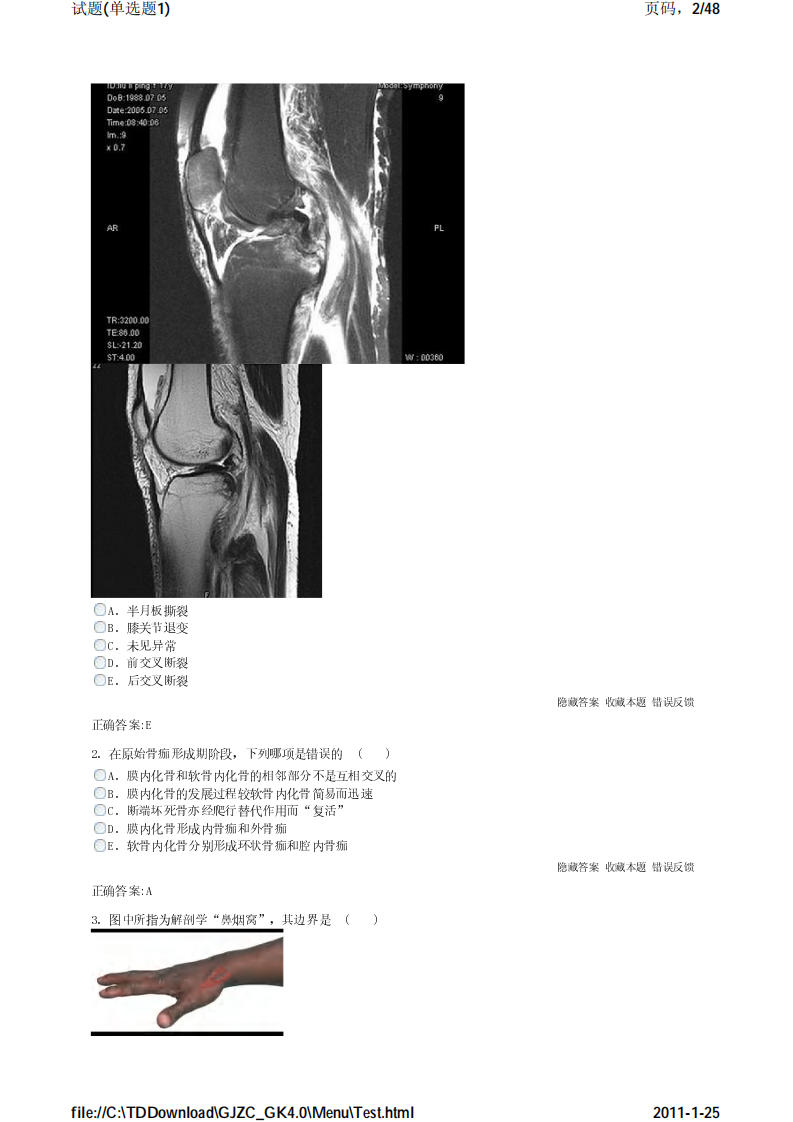

考试宝典 医学高级职称考试 骨科 单选题1.pdf

骨科